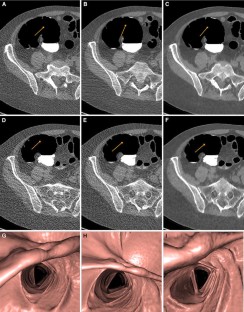

Twenty patients underwent CTC at a standard dose in supine and prone positions and at a reduced dose in the supine position. All other scan parameters (except noise index) were held constant. Acquisitions were reconstructed using 3 algorithms: filtered back projection (FBP), adaptive statistical iterative reconstruction (ASIR), and MBIR. Noise was assessed quantitatively by comparing the SD in Hounsfield units at 5 standard locations. Qualitative assessment was made by 2 experienced radiologists blinded to technique who subjectively scored image quality, noise, and sharpness (from 0 to 4).

The standard-dose and reduced-dose CT dose index/dose-length product were 6.7/328 and 2.7 mGy/129 mGy-cm, respectively (60 % reduction). Measured mean noise level increased from the standard to the reduced dose (FBP, from 58.6 to 97.2; ASIR from 35.8 to 60.6; and MBIR from 16.6 to 21.9). MBIR had significantly less noise than ASIR on 2-dimensional images at both standard and reduced doses (P < .01).

Radiation dose in CTC using MBIR can be reduced by 60 % while maintaining image quality and reducing image noise.